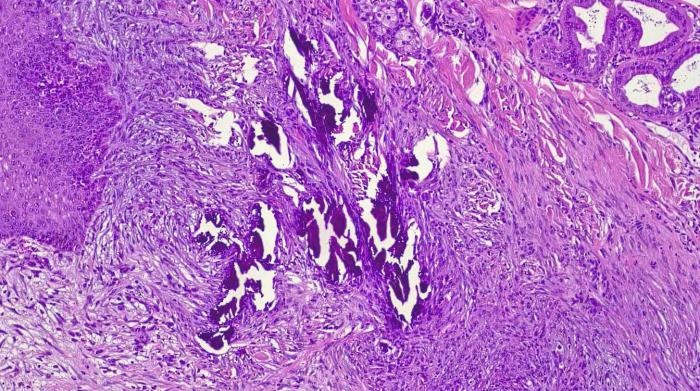

Durante la biopsia se observó salida de material amorfo, semisólido y blanquecino. El estudio histopatológico confirmó que se trataba de una calcinosis circunscrita por la presencia de dépositos de calcio (Figura 6 y 7).

Histológicamente, la CC se caracteriza por la presencia de material basofílico amorfo o granular, rodeado de reacción inflamatoria granulomatosa con macrófagos espumosos y células gigantes multinucleadas, a menudo encapsulado por tejido conectivo fibroso7,12-14.